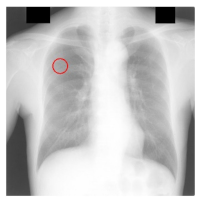

| Filename | Image | JSRT Metadata Notes | Radiologist Observations |

| JPCLN151.png | ![]() | Extremely subtle 14 mm |

Extremely subtle Behind cardiac silhouette Overlaps vascular marking |

| JPCLN003.png | ![]() | Obvious 30 mm |

Obvious Overlaps vascular markings |

| JPCLN130.png | ![]() | Extremely subtle 30 mm |

Extremely subtle Behind cardiac silhouette |

| JPCLN141.png | ![]() | Extremely subtle 10 mm |

Extremely subtle Behind rib/clavicle |

| JPCLN142.png | ![]() | Extremely subtle 10 mm | Not visible. |